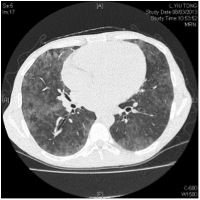

A man with known history of Crohn’s disease in remission, end stage renal failure on peritoneal dialysis was incidentally found to have diffuse parenchymal infiltrate in the CXR. High resolution CT showed diffuse ground glass opacities (picture 3).

As a result of that, the patient might need to go through a long list of investigations. After assessing this patient and reviewed the CT images; we found that there was significant discordant between the alarming CT features and the totally asymptomatic clinical status. This discordance made metastatic calcification the most likely diagnosis. Bone scan was then arranged(picture 4) which showed intense uptakes in patient’s both lungs that almost equal to the uptake of bone.